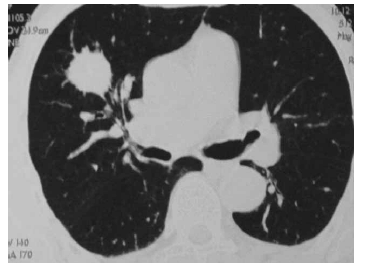

Considerando o caso clínico de um paciente cujo exame de imagem é reproduzido acima, julgue os próximos itens.